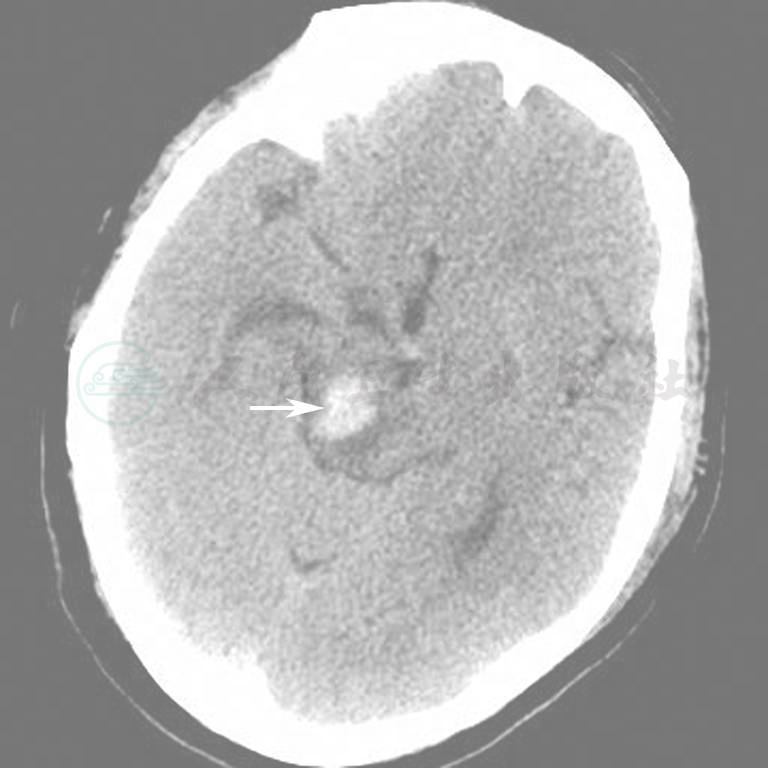

图9  脑干右份出血

图10  颅内出血(硬膜外)